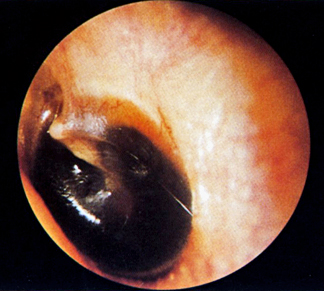

| Normal Tympanic Membranes | ||||

![]() |

Abnormal tympanic membranes |

|

EARS: lacerations, discharge, hearing grossly intact, hemotympanum, Battle’s Sign/mastoid ecchymosis (Base of Skull/Middle Cranial Fx),

- Hearing: air conduction, bone conduction, tympanic membranes intact